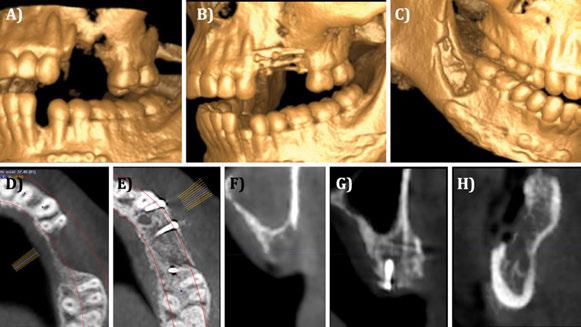

Figura 1. Caso clínico con membrana no reabsorbible (Goretex®). A) Situación radiográfica (2D) basal. B) Situación radiográfica (3D) basal.

Figura 2. Caso clínico con membrana no reabsorbible (Goretex®).

Figura 3. Caso clínico con membrana no reabsorbible (Goretex®). Continuación. A) Fresado para la colocación del implante. B) Colocación del implante en la posición tridimensional adecuada. C) Relleno del defecto óseo con `chips´ de hueso autólogo del propio paciente.

Figura 5. Caso clínico con membrana no reabsorbible (Goretex®). Continuación. A) Sutura y cierre primario. B) Situación radiográfica 2D inmediata post-operatoria.

Figura 6. Caso clínico con membrana no reabsorbible (Goretex®). Continuación. A) Reentrada. Vista vestibular. B) Reentrada. Retirada de la membrana. Vista vestibular. C) Reentrada. Retirada de la membrana. Vista oclusal. D) Aspecto oclusal-crestal del implante. reabsorbibles frente a un 90,9% de los implantes colocados tras injertos de bloque autólogos, a 2 años de seguimiento tras la carga protésica. En relación al tipo de politetrafluoretileno (PTFE) que se puede utilizar en estas membranas no reabsorbibles, es necesario distinguir que el clínico tiene a su disposición membranas de PTFE denso (d-PTFE) o expandido (e-PTFE), siendo las segundas las que más respaldo científico tienen en la actualidad (Urban y cols 2019).

Figura 4. Fijación de la membrana no reabsorbible (Goretex®).

7. Caso clínico con membrana no reabsorbible (Goretex®). Continuación. A) Injerto de tejido conectivo autólogo. B) Sutura y cierre primario. C) Situación radiográfica tras carga protésica. D) Situación clínica tras carga protésica.

8. Caso clínico con membrana no reabsorbible (Goretex®). Comparación en vista oclusal. A) Defecto óseo inicial. B) Situación ósea en reentrada. C) Contorno vestibular tras carga protésica.